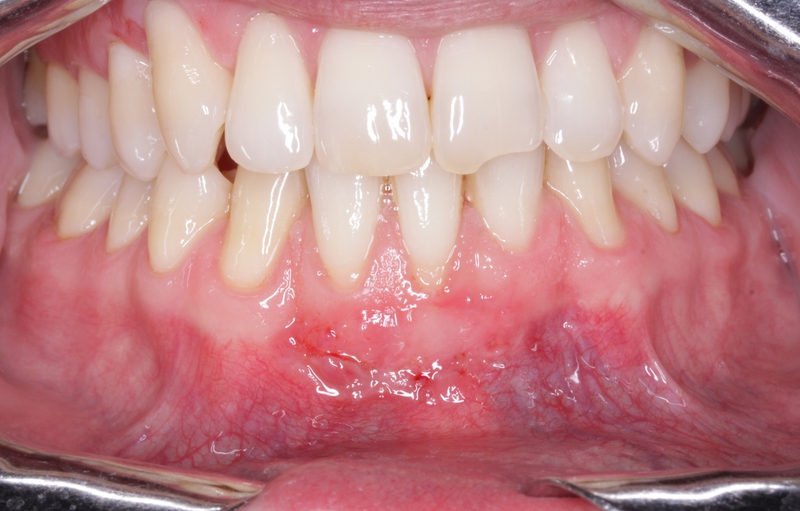

ESTADO PREVIO